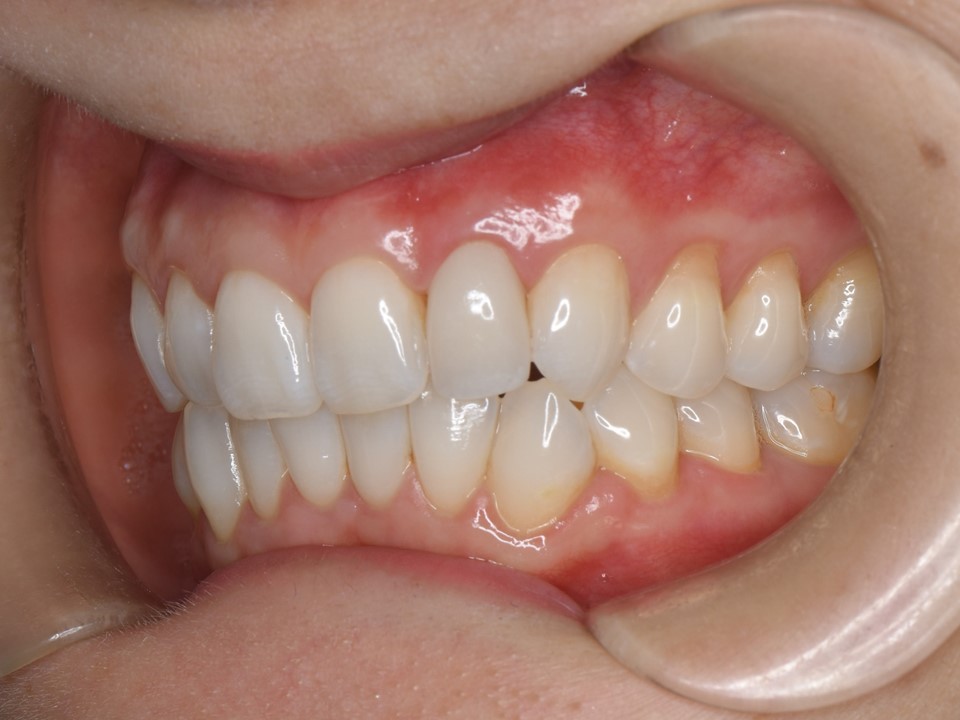

初診時口腔内。左側側切歯(⇒)のブラックマージンを主訴に来院。セラミッククラウンの色も透明感が無く、審美的な改善を希望。

装着してあるセラミッククラウンが不適合のため、歯茎に炎症を認める。